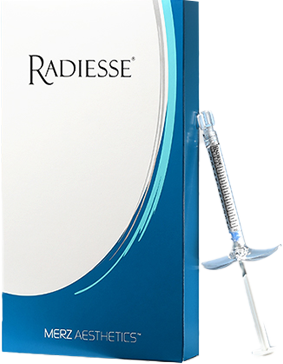

콜라겐 구조의 70%

클로인,프롤린,라이신은 콜라겐의 70%를 차지합니다.

섬유아세포가 대사활동을 하는 동안 섬유아세포에 자극을 주어

콜라겐을 생성하거나, 콜라겐이 서로 합성되는 현상이 일어납니다.

탄력 개선